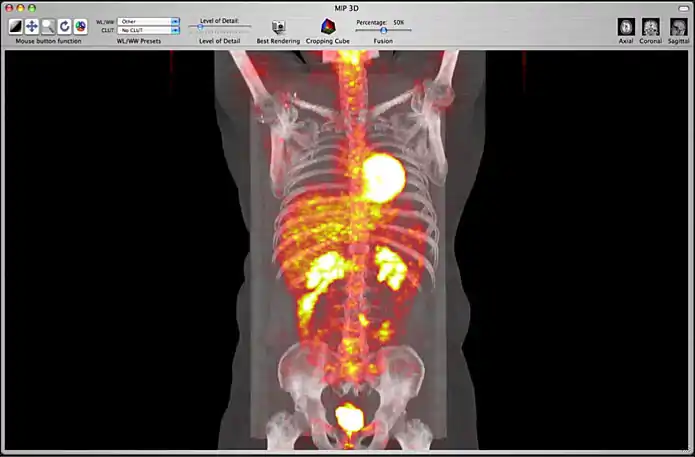

Image fusion is also available for 2D and 3D reconstructions implying that you can use image fusion along with MPR, Volume rendering, etc...

Image fusion in the 3D MIP window